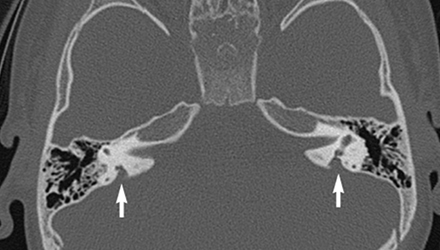

SLC26A4基因定位于人類染色體7q31,SLC26A4基因和大前庭導水管綜合征相關突變位點的發現,證實SLC26A4是大前庭導水管綜合征的責任基因。

我們平時提到的“一巴掌打聾”、“一跤摔聾”其實都與SLC26A4基因突變有關,絕大多數大前庭導水管綜合征都是SLC26A4基因突變惹的禍。

SLC26A4基因編碼一種叫“Pendrin”的跨膜轉運蛋白,在機體離子成分平衡的維持中發揮重要作用。

在內耳,Pendrin表達于內淋巴管、內淋巴囊、橢圓囊、球囊等處,異變的蛋白將對這些結構的正常生理功能產生影響,引發聽損。

聽力損失表現:

SLC26A4基因突變導致的大前庭導水管綜合征的典型表現為兒童時期的聽力損失,90%的患者為雙側性,聽力損失程度不一,可表現為接近正常或重-極重度。

病程可為穩定性、進行性或波動性,聽力可逐步下降至全聾;跌倒、撞擊等行為或無外界影響都可能引發聽力的下降。